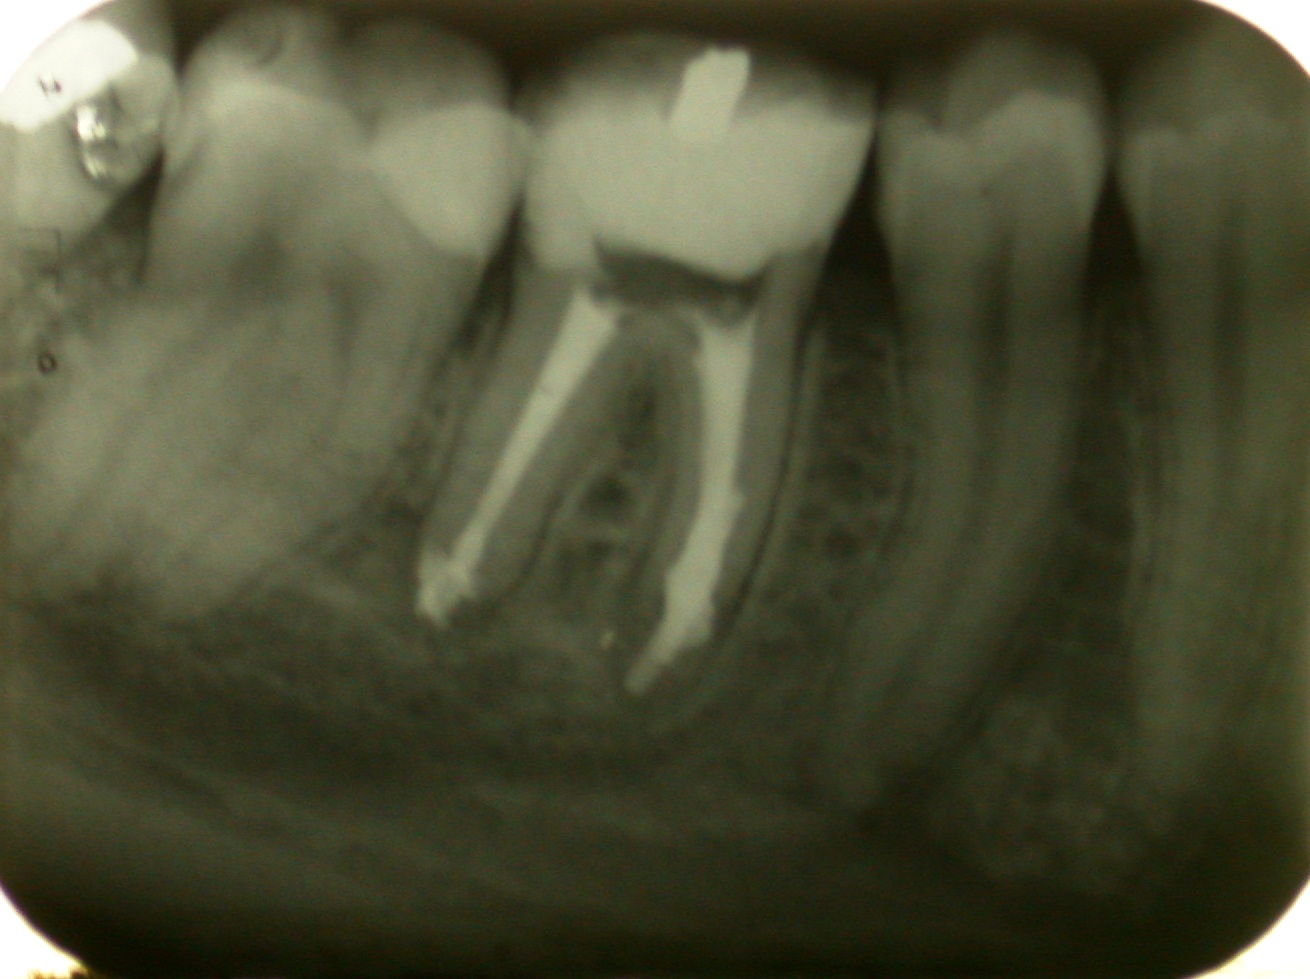

La paziente giunge alla nostra attenzione con un dente già trattato endodonticamente e con un ritrattamento iniziato da altro operatore circa un anno prima e mai terminato. La paziente ha iniziato a lamentare dolore e mostrava il viso tumefatto a causa di un ascesso endodontico a partenza dal molare in oggetto. Il dente è stato ritrattato endodonticamente e chiuso con guttaperca e pulp canal sealer. Tra la prima e la seconda seduta (a distanza di 15 giorni l'una dall'altra) il dente è stato medicato con idrossido di calcio. Il follow up è a 10 anni.

Ritrattamento endodontico di molare inferiore con lesione periapicale, rizolisi apicale e riassorbimento interno.

Il caso mostra un molare inferiore con un quadro complesso di riassorbimento apicale per presenza di lesione infiammatoria apicale cronica. Il dente mostra anche un riassorbimento interno.

Prova dei coni con sorgente radiogena disassata per consentire la visualizzazione di tutti i canali.